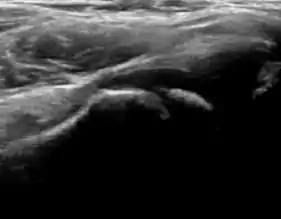

Figure 11:

Useful ultrasound measures in neonatal hip sonography, alpha and beta angles.[1]

Measurement of femoral head coverage.[1]